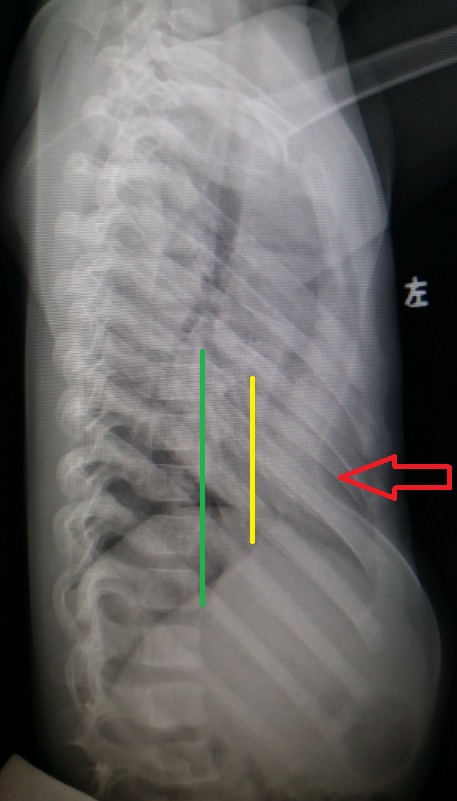

上半胸壁扁平 ,前胸壁广泛凹陷图1,胸部凹陷最深处位于剑突上方约2cm

入院查体发现,患儿胸前重度凹陷,以剑突附近明显.

畸形,是指形成前胸壁的胸骨,部分肋骨及肋软骨向脊柱方向的漏斗状凹陷

中度以及重度,主要计算方法是根据胸骨凹陷后缘后面到脊柱前缘的距离